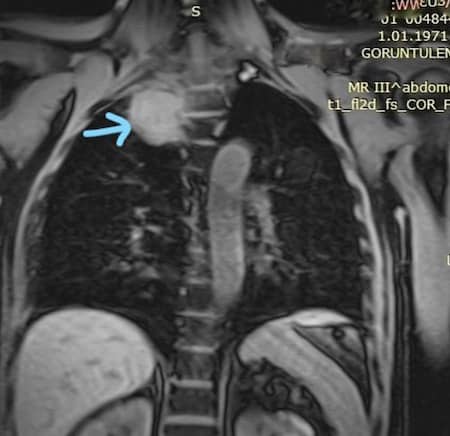

Онкологические заболевания легких лидируют в числе тех, которые ежегодно диагностируются во всем мире. При обнаружении на ранней стадии их лечение в множестве случаев дает положительные результаты. Но проблема заключается в том, что диагностируют рак легких часто уже тогда, когда болезнь проявляется более поздними симптомами. То есть он может успеть поразить и другие органы и системы.

Стоит отметить, что данное явление не всегда явлннеяется признаком онкологии, хотя иногда и указывает на то, что опухоль развивается в верхушечносм сегменте легкого рядом с нервными сплетениями. Симпатические повреждения или поражения второго нейрона (чуть ниже верхнего шейного узла) могут спровоцировать изменение зрачка в размере.